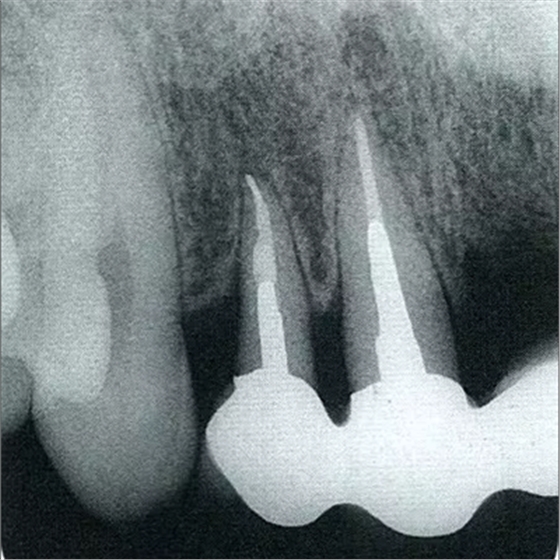

圖10-2 x片顯示的遠(yuǎn)中部有垂直性骨缺損。

圖10-10 術(shù)后2年的x片。確認(rèn)骨水平獲得改善,牙周探診值在2mm以下